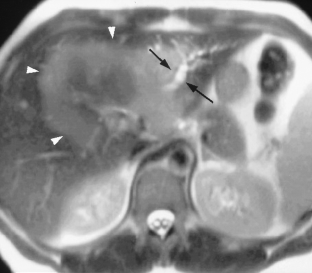

Cholestasis may result from hepatocellular (intrahepatic) disease or biliary tract (extrahepatic) abnormalities. Etiologies causing extrahepatic cholestasis are extremely diverse and invasive procedures, such as endoscopic retrograde cholangiopancreatography (ERCP) and percutaneous transhepatic cholangiography (PTC), were previously required to establish the diagnosis. Due to refinements of magnetic resonance imaging (MRI) techniques, the patient with extrahepatic cholestasis currently can be evaluated noninvasively, and the information revealed frequently exceeds the findings obtained by ERCP and PTC. In this essay, we illustrate the classic MR cholangiographic (MRC) and MRI features of a variety of disorders causing extrahepatic cholestasis, including non-neoplastic disorders of the biliary tract (congenital abnormalities, infectious processes, iatrogenic disorders, and postsurgical complications) and neoplastic conditions (e.g., tumors of the pancreas, biliary tree, liver, ampulla, and regional lymph nodes). In most cases, familiarity with the key MRC features in addition to information obtained via cross-sectional MR images provide sufficient information for adequate lesion characterization.